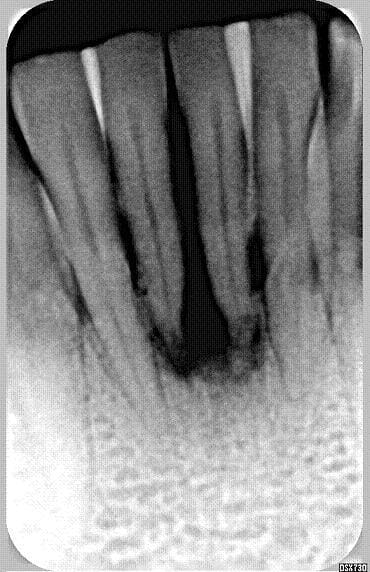

j’ai regardé la radio 76578990 fois… bin waow…

combien de temps entre le debut et la seconde radio .. la cicatrisation d'un cas comme ca en naturel c'est 8 mois mini

cicatrisation à 6 mois

par contre je suis persuadé qu'il ne faut pas sonder pas irriguer plus qu'il ne faut surtout si comme dans le cas ou celui de Carole la composante occlusale prend le dessus sur la composante infectieuse .. Si abcès en urgence atb probabiliste de type metronidazole ...pas de tests . J'ai mis volontairement la sonde sur la photo pour montrer qu'à 6 mois seulement j'avais sondé pas avant.au niveau muqueux c'est cicatrisé mais au niveau osseux il faut encore 3 mois au moins